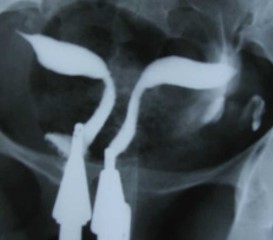

UTERINE MALFORMATION

• Uterine malformations are congenital defects of a woman’s uterus occurring in about 5% of women

Types of malformation

Bicornuate :

• The uterus appears heart shape with a deep indentation starting at the top of the uterus.

Septate :

• The uterus appears normal from outside but contains an internal wall or septum that divides the uterine cavity into two.

Didelphys :

• double uterus where the two halves of the uterus remain completely separate

Unicornuate :

• Only one half of the uterus is well developed.

Diagnosis :

• Mostly discovered during investigation for infertility as they are usually asymptomatic

• 3D ultra sound

• HSG

• MRI

• Diagnostic hysteroscopy